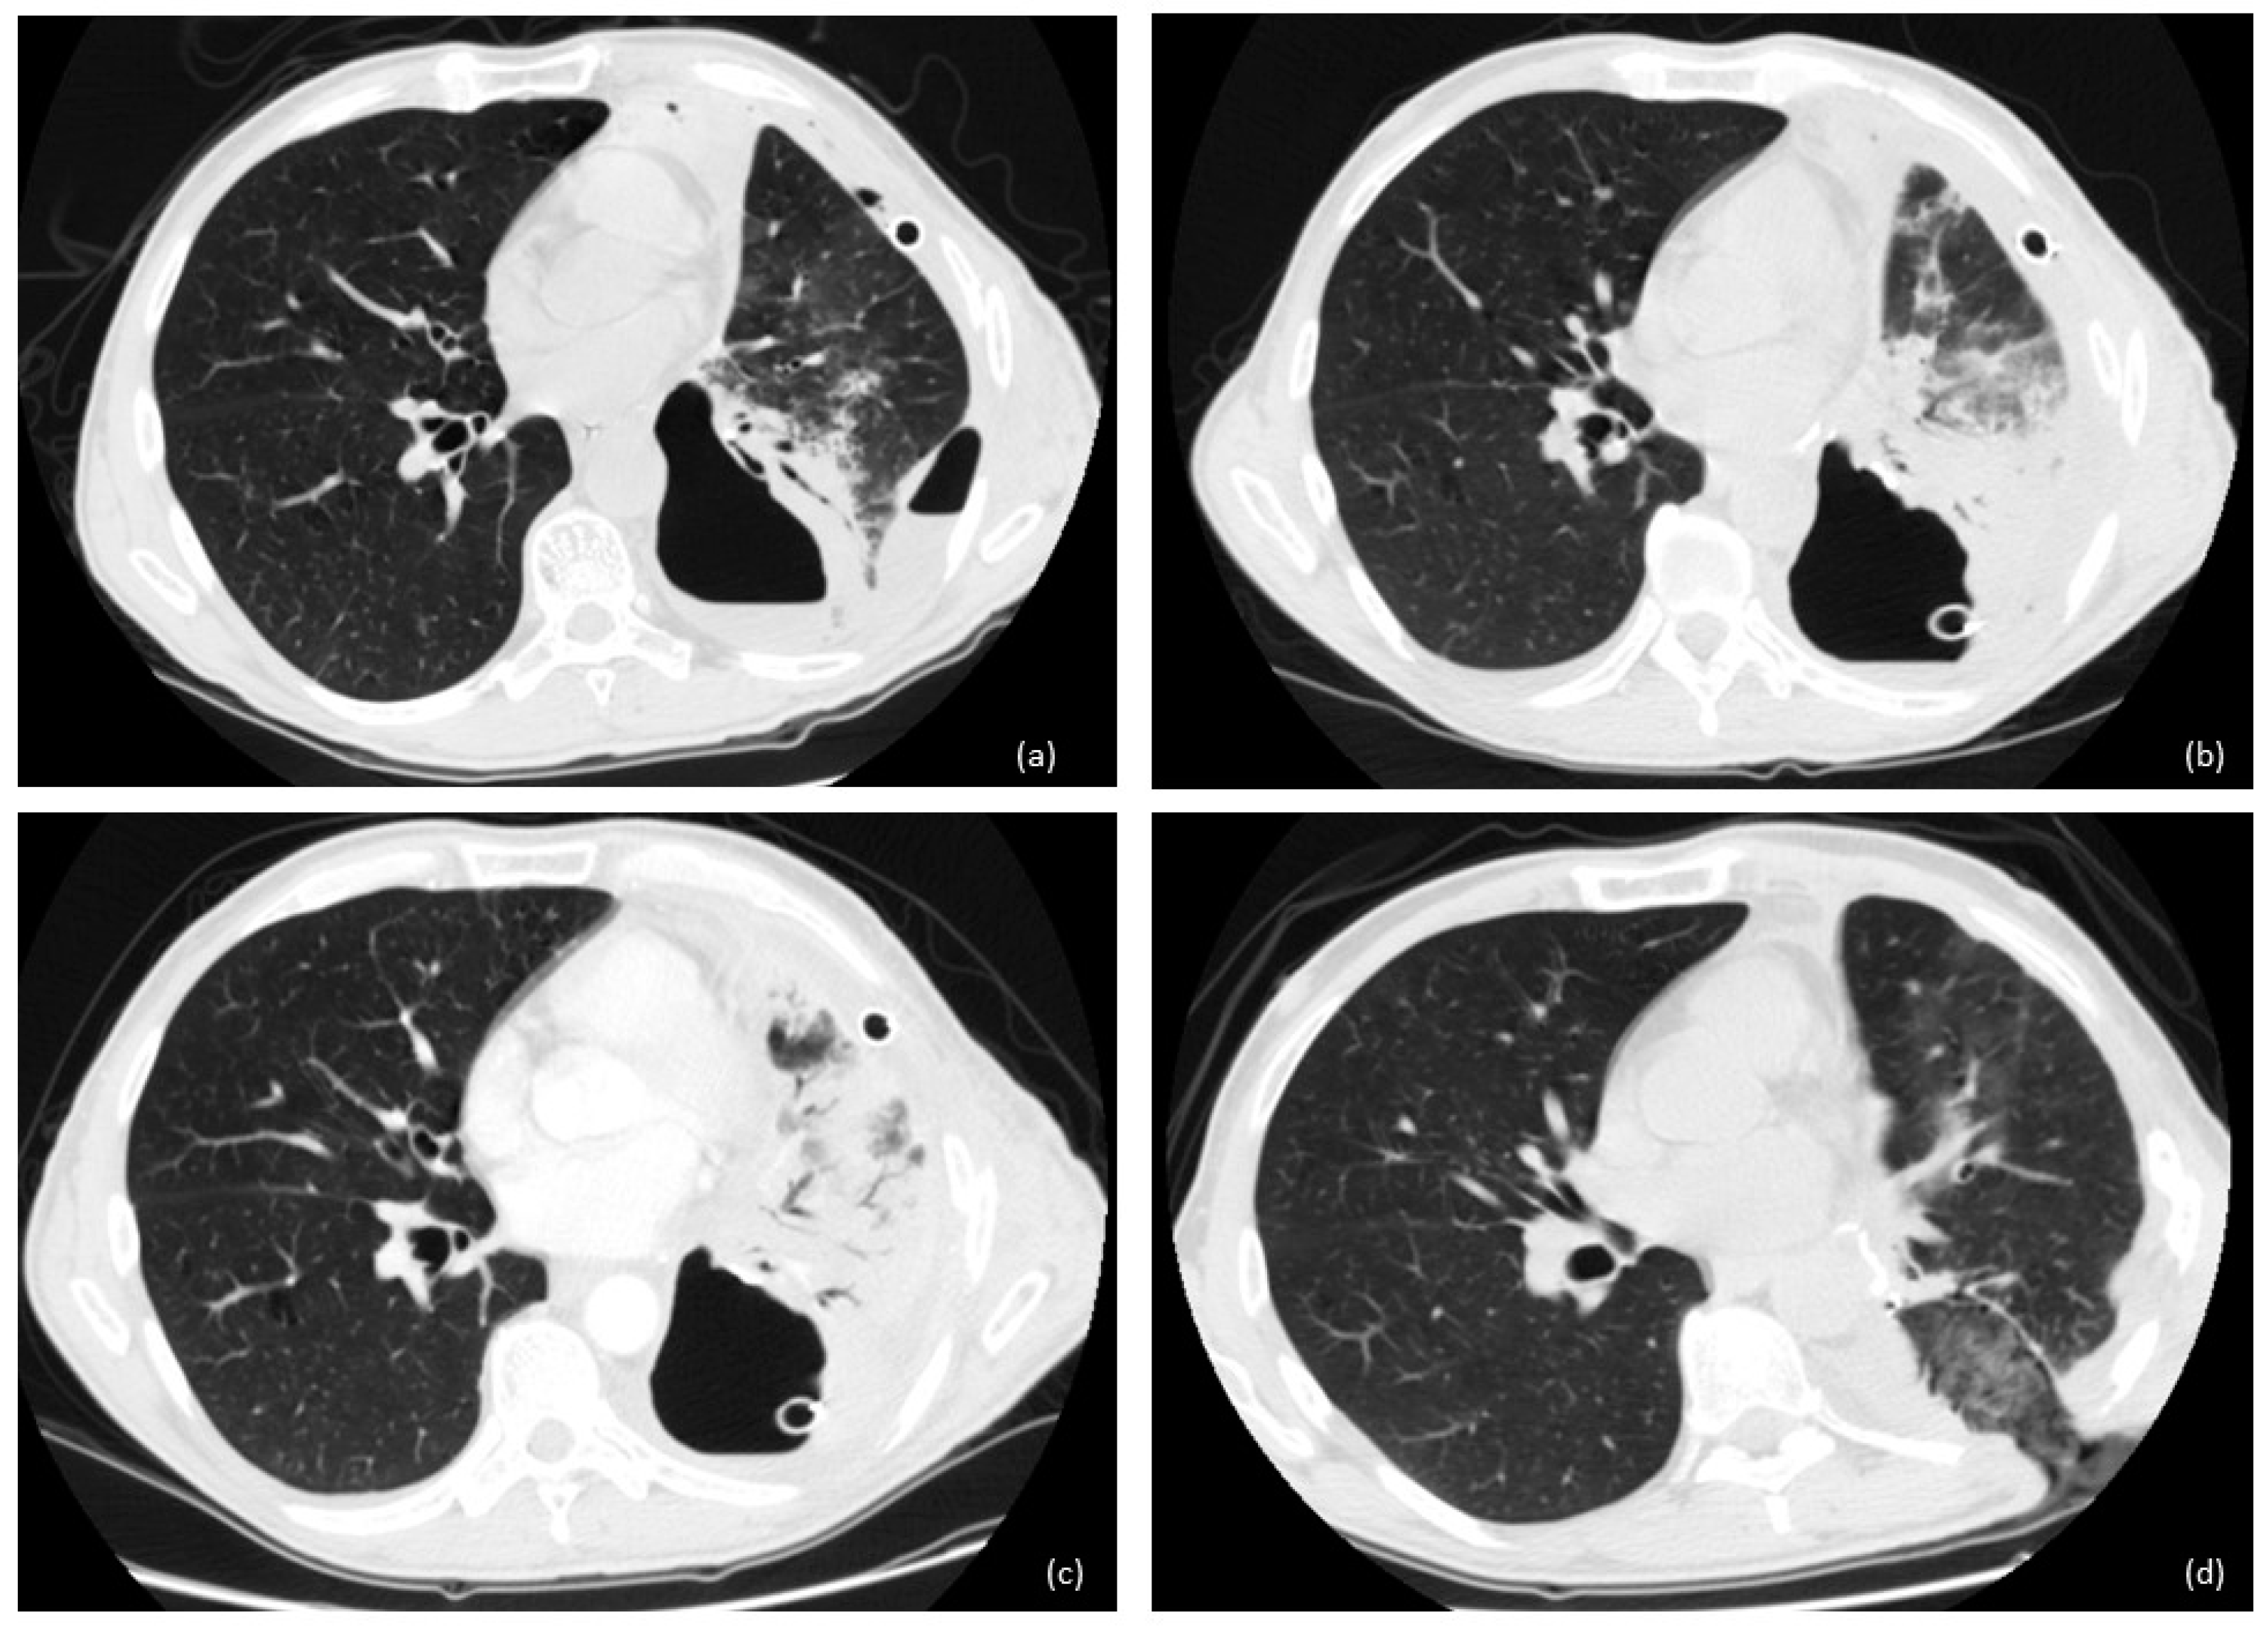

2.3. New Therapeutic Horizons: Percutaneous Treatment of Small and Late BPF